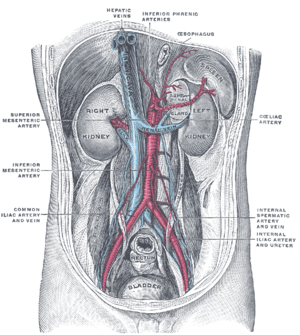

| The nutcracker syndrome results from compression of the left renal vein between the aorta and the superior mesenteric artery. | |

The nutcracker syndrome (NCS) — is a manifest variant of nutcracker phenomenon, renal vein entrapment syndrome, or mesoaortic compression of the left renal vein. It results most commonly from the compression of the left renal vein between the abdominal aorta (AA) and superior mesenteric artery (SMA), although other variants exist.[1][2] The name derives from the fact that, in the sagittal plane and/or transverse plane, the SMA and AA (with some imagination) appear to be a nutcracker crushing a nut (the renal vein). There is a wide spectrum of clinical presentations and diagnostic criteria are not well defined, which frequently results in delayed or incorrect diagnosis.[1] This condition is not to be confused with superior mesenteric artery syndrome, which is the compression of the third portion of the duodenum by the SMA and the AA.